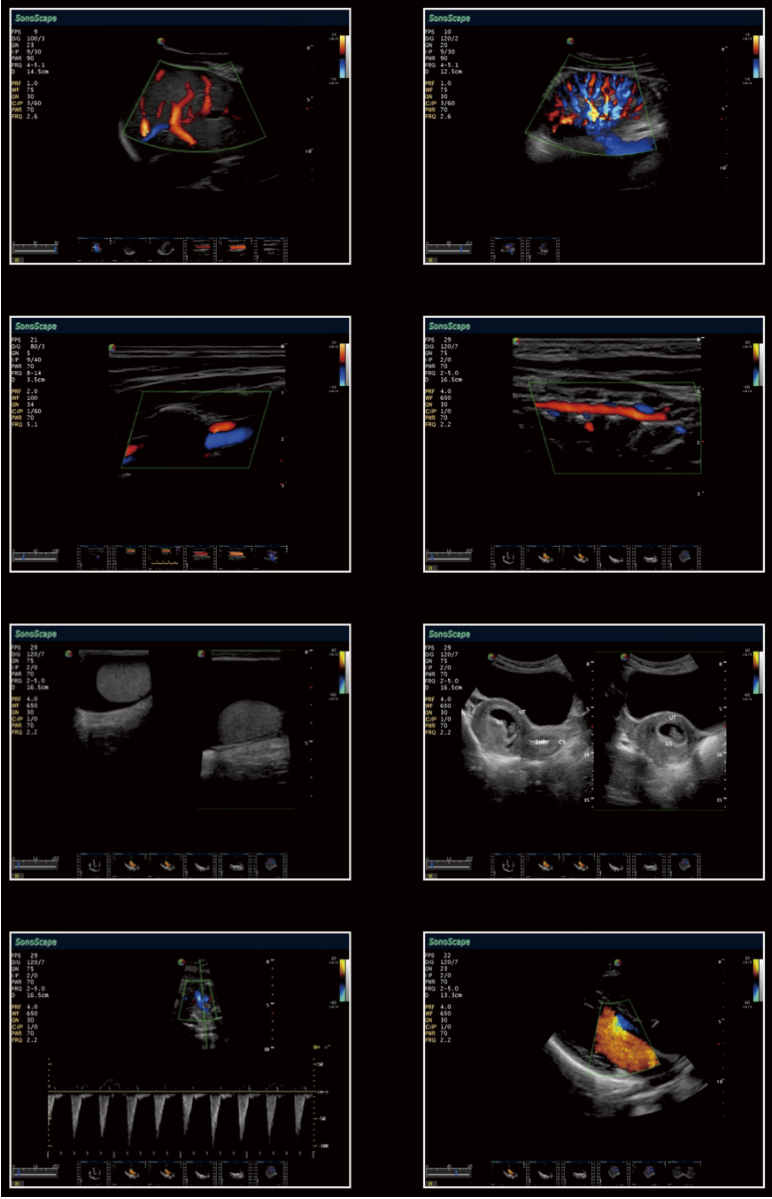

El S9 proporciona una imagen panorámica en tiempo real para órgano voluminoso y masas para la facilidad de medición y eficiencia diagnóstica, generando rápidamente información exacta sobre la posición de las lesiones.

Detecta los detalles más temprano en el primer trimestre en los exámenes de ginecología, mejora su confianza en el diagnóstico. A excepción de la calidad de 3D/4D, S9 también permite excelente imagen 2D bajo diagnóstico 3D/4D endovaginal, lo que aumenta la capacidad de diagnóstico y de la satisfacción de las pacientes obstétricas.

S9 puede proporcionar una alta densidad de la sonda phased array para satisfacer las necesidades tanto de alta velocidad de fotogramas y la resolución de image premiun en la obtención de imágenes cardíacas. Gracias por la alta sensibilidad de mapeo Doppler color del SonoScape, S9 muestra el diagnóstico cardiaco precisa más allá de su imaginación.

S9 dota con el nuevo método para apoyar los ecografistas en la evaluación de la elasticidad del tejido. Las diferencias en las respuestas de los tejidos se detectan y se visualizan en tiempo real por los algoritmos de elastografía a través de diferentes representaciones gráficas.

Estrés echo el paquete con la interfaz totalmente integrado y de fácil programación para personalizar sus necesidades. Todas funciones combinan con S9, para entregar el flujo de trabajo optimizado para la puntuación movimiento de la pared y la presentación de informes.